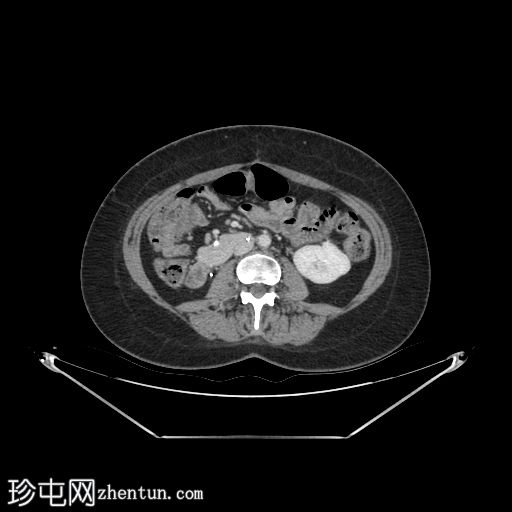

轴位增强扫描

门静脉期

左髂窝肾移植(轴位、冠状位),显示移植肾与同侧髂总血管的动脉和静脉吻合。移植肾形态完整,实质均匀强化。

本例中,影像学检查显示原位肾脏和胰腺明显萎缩,符合长期糖尿病合并慢性肾脏病的表现。肾移植位于左髂窝,与同侧髂血管的动脉和静脉吻合通畅,肾实质均匀强化,这些影像学表现均符合功能性肾移植的影像学特征。移植胰腺位于右侧腹膜后,形态和位置均符合原位胰腺,供体十二指肠袢与原位十二指肠吻合良好。